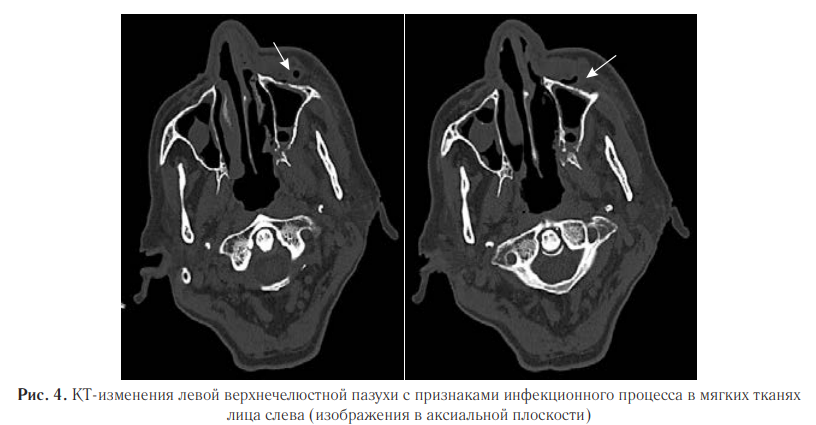

В левой верхнечелюстной пазухе наблюдали деструкцию и истончение переднелатеральной стенки, а также отек и утолщение мягких тканей лицевой области слева с пузырьками воздуха (рис. 4).